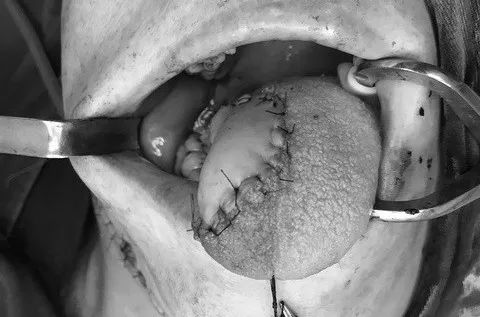

陈先生的右侧舌缘有约3.0*2.5cm大小的肿瘤,肿瘤表面有大小约1*1cm的溃疡面,表面被覆黄白色假膜。

经过全身情况评估之后,陈先生被推进了手术室,切除这块长在舌头上的“怪物”。

切掉“怪物”后陈先生,舌头几乎没了一大半。这也就意味着,以后说话和吃东西都成问题。

为此,医生选择了一条不同以往常规的路——用陈先生上臂外侧的一块肉,“移花接木”到舌头上。

“上臂外侧皮瓣厚度适中,特别适合舌体缺损的修复。”张国权说。

所幸的是,最后陈先生的舌头修复部位恢复良好,10天后,他就康复出院了。复查时也发现,他的舌头功能没受到影响,可以清楚说话和正常饮食。